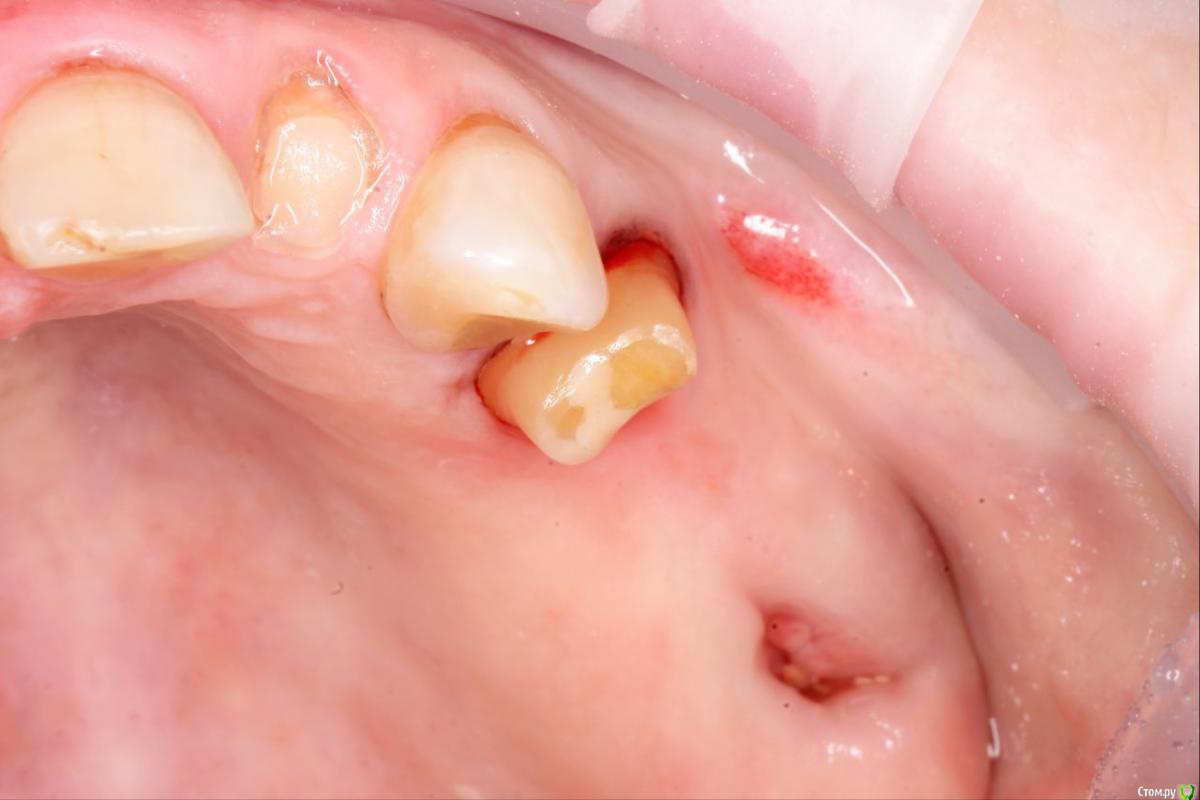

ivan26 Опубликовано 7 октября, 2017 Поделиться Опубликовано 7 октября, 2017 Коллеги, вкратце ситуация: снял коронку, зуб витальный. Решено поставить литую коронку.Как ,в данном случае, будет правильнее создать границу препарирования?На снятой коронке границе были апикальный сулькуса.Правильно я понял, что сначала тримером десну убрать и отдавить ее времяшкой на пару недель? Ссылка на комментарий

Klyu4n!k Опубликовано 10 октября, 2017 Поделиться Опубликовано 10 октября, 2017 и как эти задачи друг другу противоречат?что мешает оставить его витальным с новым уступом? Согласен, не вижу никаких помех. Анестезия, ретракция, полировочным бором обозначить уступ, оттиски. По фото не похоже на преп под штамповку, вполне прилично обработано. Ссылка на комментарий

BasDent Опубликовано 10 октября, 2017 Поделиться Опубликовано 10 октября, 2017 Вообще по фото есть ощущение, что там тонкий плавный уступ 135 градусов. Ссылка на комментарий

Pan Опубликовано 10 октября, 2017 Поделиться Опубликовано 10 октября, 2017 преп явно не под штамповку, и уступчик вроде есть, но и новый сделать не проблема. Ссылка на комментарий